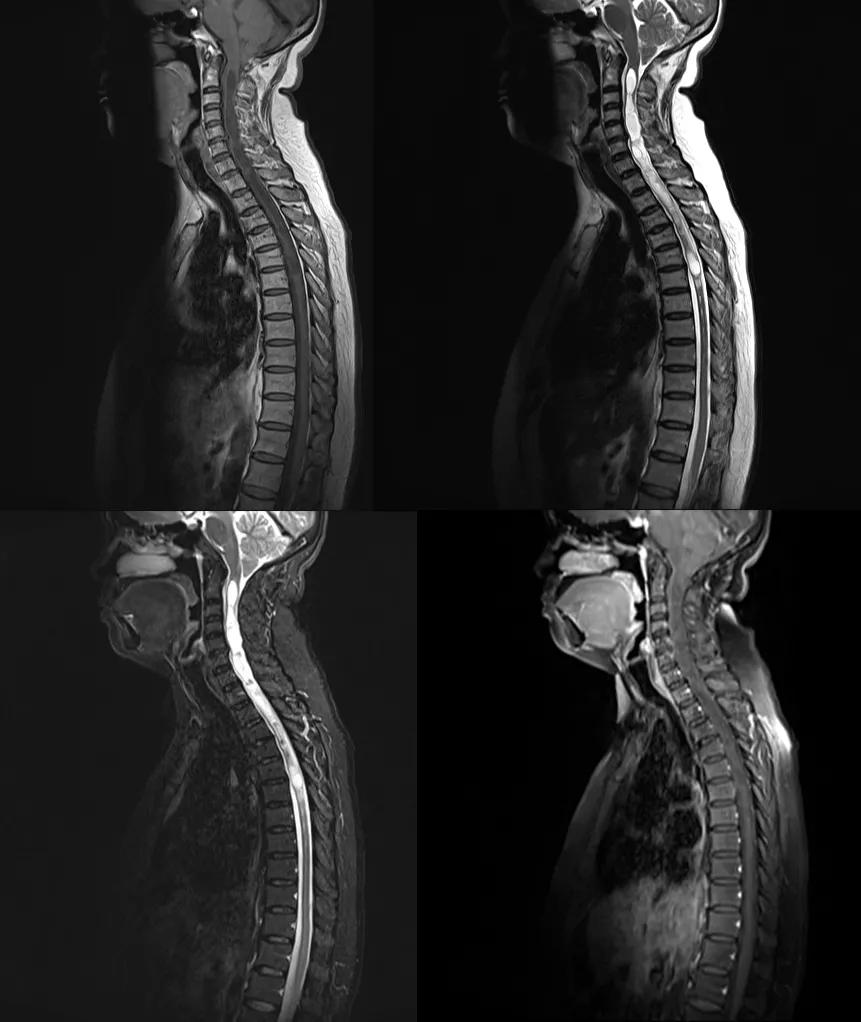

先天性颅底凹陷

先天性颅底凹陷症(Congenital basilarinvagination)是以枕骨大孔为中心的颅底骨组织、寰椎及枢椎骨质发育畸形

枕骨大孔周围的颅底骨向上方凹陷进入颅腔,并使之下方的寰枢椎,特别是齿状突升高甚至进入颅底,并引起枕骨大孔狭窄,后颅窝缩小,斜坡升高和环枕重叠等一系列畸形改变,是枕大孔区最常见的畸形

该病诊断的径线测量方法很多,但常用的是钱氏线(Chamberlain』line),亦称枕线,由硬腭后缘向枕大孔后上缘作一连线,正常人齿状突在此线 3 mm 以下,若超过即为原发性颅底凹陷症

case 1:女性,56 岁,反复头痛、头晕及双上肢麻木 5 月余。

诊断:颅底凹陷症并颈段脊髓变性。